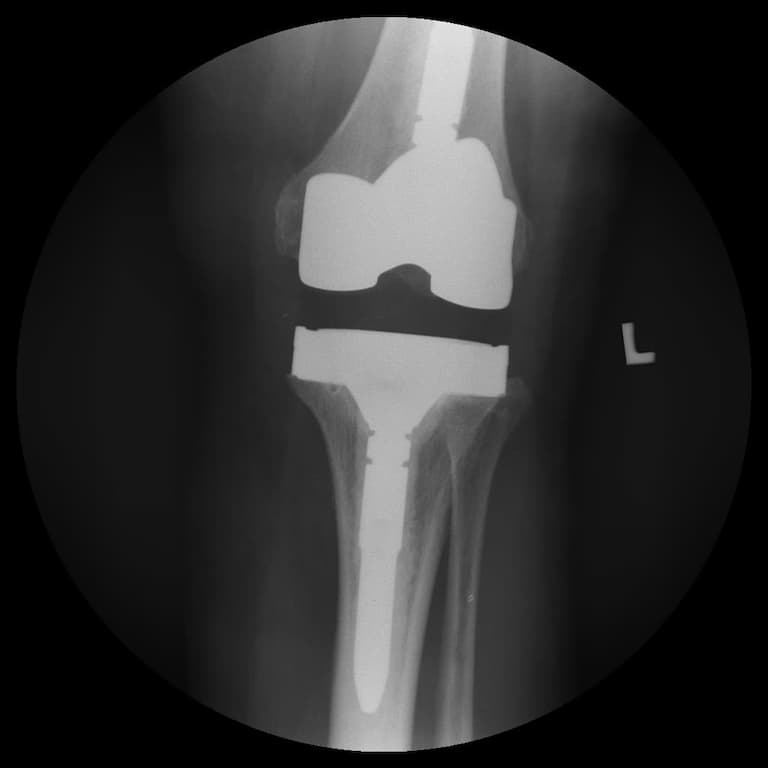

Үе дайрсан ясны анхдагч хавдар, ясны дутмагшлын үед хийгдэх мэс засалimg20Үе дайрсан ясны анхдагч хавдар, ясны дутмагшлын үед хийгдэх мэс засалimg21

Зураг 3. Мэс заслын дараах рентген зураг. Эгц урд, хажуугаас авсан байдал

Энэ тохиолдолд үений шөрмөсөн холбоос хэвийн хадгалагдаж үлдсэн байсан. Хиймэл үе - ястай тогтвортой сайн бэхлэгдэх нөхцлийг хангах чөмөгт гол руу орсон уртасгагч – extension stem-тэй хиймэл үе.